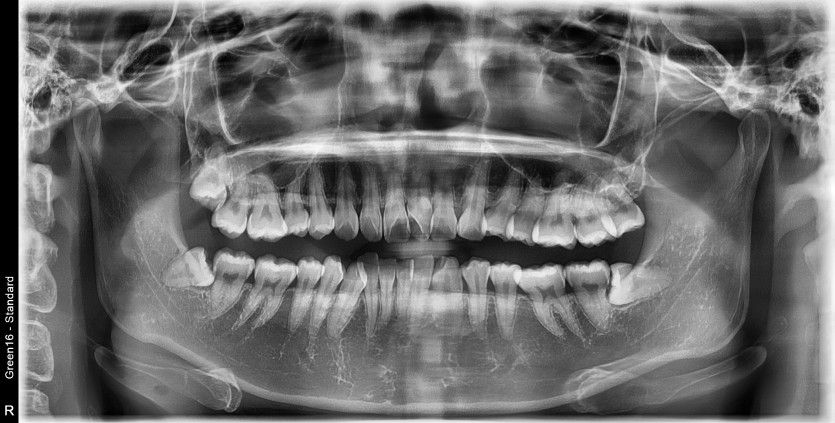

#48 사랑니 발치

구강 외과 전문의가 당일 발치했습니다.